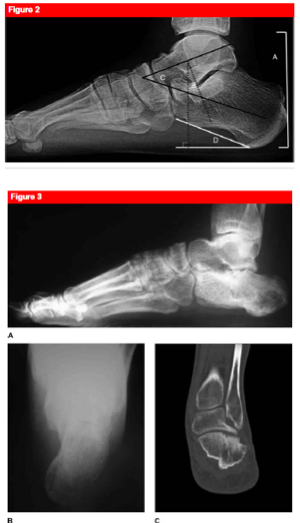

What are the typical radiographic measurements of a calcaneus fracture